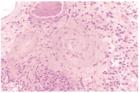

病變主要侵犯微靜脈、微動脈、毛細血管,在血管壁有中性粒細胞或淋巴細胞浸潤、白細胞核破碎及血管壁纖維蛋白樣壞死。

5、微動脈或靜脈活檢示血管壁或血管外圍有粒細胞浸潤。

美國 1990 年超敏性血管炎分類診斷標準為:①發病年齡>16 歲;②發病前服藥史;③隆起性紫癜,壓之不褪色;④斑丘疹(一處或多處皮膚大小不等、扁平、突出皮表);⑤皮膚活檢示微動脈或微靜脈血管壁或血管外圍有中性粒細胞浸潤。以上5項中具備3項或以上者即可診斷超敏性血管炎。但有些患者找不到誘發因素,而症狀持續不減,呈慢性經過者,常需與過敏性紫癜、冷球蛋白血症、顯微鏡下多血管炎、低補體血症蕁麻疹性血管炎等鑑別。